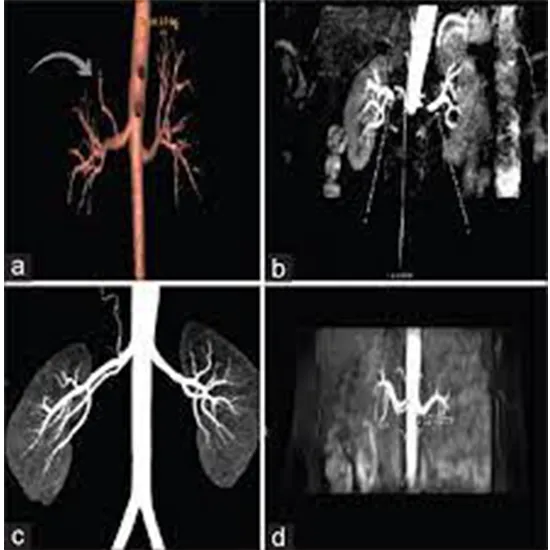

A renal angiography is a type of imaging test that examines the blood vessels in your kidneys. It can be used by your healthcare provider to examine blood vessel ballooning (aneurysm), blood vessel narrowing (stenosis), or blood vessel blockages. He or she can also assess how well blood flows to your kidneys.

The radiologist injects a contrast dye into the artery that leads to the kidney for the test. The dye is then observed as it flows through the blood vessels in the kidneys using X-ray images. A renal angiogram may be required to assist your healthcare provider in detecting problems in your kidney's blood vessels. These issues may include: Blood vessel enlargement (aneurysm)